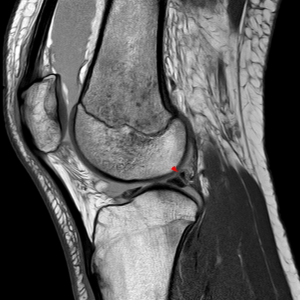

Meniscus tear injury to the knee happens in car accidents with great frequency. Symptoms usually involve popping or other noises which can be audible when the knee is moved. Meniscus tear knee injuries often occur when the knee hits the dash and there is an initial bruise. An MRI is an important tool used to identify a meniscus tear which can be full or partial. Meniscus tear injuries may impair and hinder one’s walking without a noticeable limp or gait impairment.